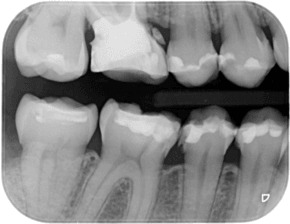

Байтуинг (Bitewing)

Байтуингът е един от методите за диагностициране на кариес в междузъбните контакти едновременно на горните и долните странични зъби. С негова помощ се констатира и загуба на костно вещество при пародонтит. За направата му се използва специален държател, който улеснява позиционирането.